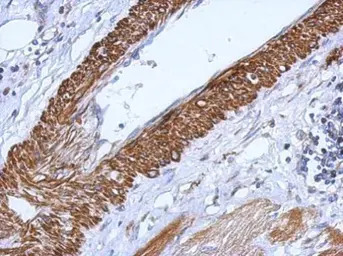

Immunohistochemical analysis of paraffin-embedded human gastric cancer, using CARD6(GTX111277) antibody at 1:500 dilution.

Antigen Retrieval: Trilogy™ (EDTA based, pH 8.0) buffer, 15min